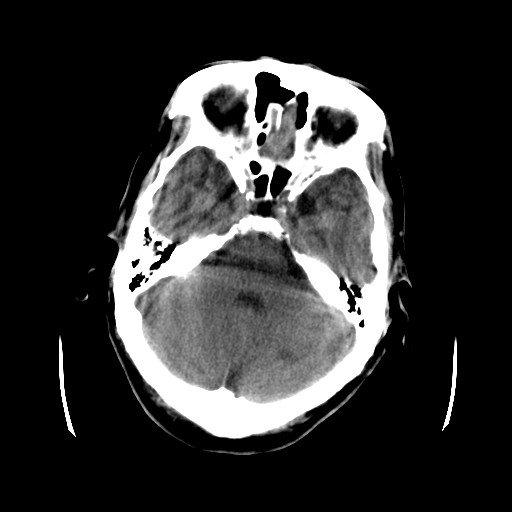

患者,男,70岁,清晨(10小时前)无法自行起床,家人无法唤醒,现昏迷,大小便失禁

左颞枕叶交界区的类圆形高密度区首先考虑脑膜瘤卒中,病人左侧小脑半球的还有多个囊性低密度,要考虑同时伴有梗塞的可能。

这个病人做ct时已经10小小时了,按说出血多稳定了,这么少的出血和这么小、少的梗塞怎么会导致病人昏迷?而脑干、脑桥和中脑都没有发现出血或梗塞,也没有明显的颅内高压,真的很奇怪。

左小脑梗塞;左顶部脑血管畸形可能;

病人昏迷是否与左顶部病变的血流突然改变(如阻断)引起脑血流动态平衡失衡有关;